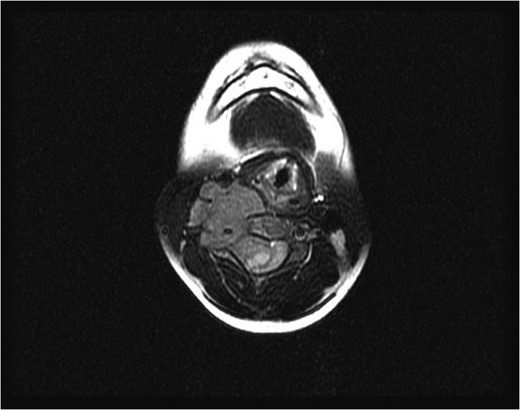

Sagittal (left) and axial (right) T1-weighted contrast-enhanced magnetic resonance images before the second surgery, showed increased size of the extraspinal component of the tumor, with kyphotic deformity of the cervical spine.